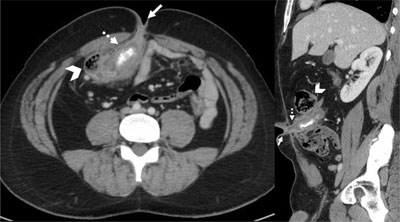

Figure 2

Coronal reformatted and axial contrast medium-enhanced CT-scan images showing dilated and thickened intestinal structure (dotted arrow) between the caecum (arrowhead) and the umbilicus (arrow), containing a calcified deposit.